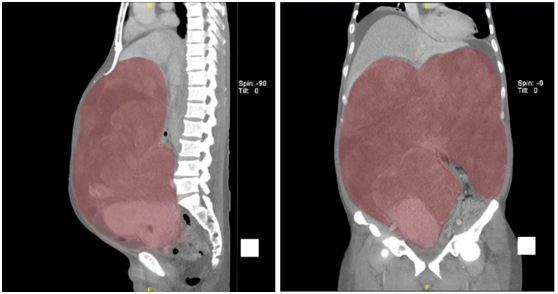

术前腹部影像

如此巨大的肿瘤,不但深入腹腔,还与多个大血管、腹腔脏器毗邻,手术风险巨大。北京大学国际医院腹膜后肿瘤外科团队在经过一系列精心的围手术期准备后,为李伯伯实施了肿瘤切除手术。手术由腹膜后肿瘤外科罗成华主任主刀,肖萌萌主治医师、陈骏主治医师配合,经过近3个小时的手术,成功切除34斤巨大肿瘤。李伯伯术后感觉良好,转入病房的当天,终于以平躺的姿势踏踏实实睡了一觉。